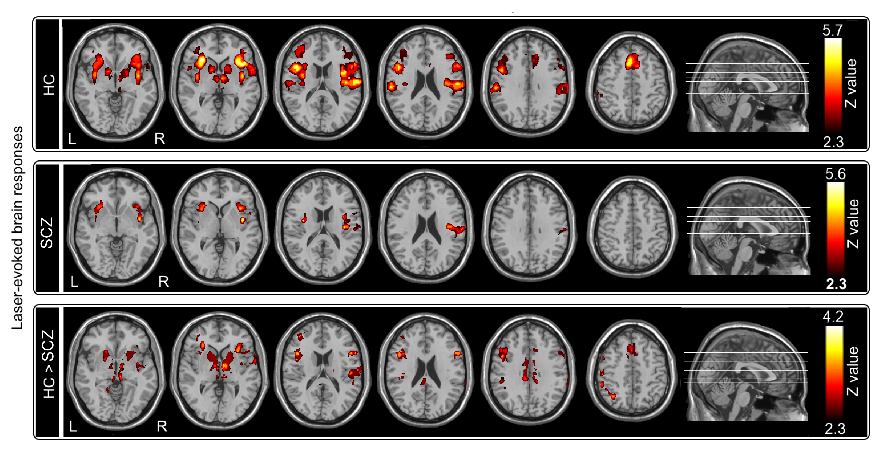

(1)与健康人群相比,精神分裂症患者对疼痛刺激不敏感,表现为患者对疼痛的主观强度评分较低、激光疼痛诱发电位各成分振幅较低和潜伏期较长(图1)、激光疼痛诱发BOLD脑响应较低(图2)。

图2 精神分裂症患者与健康人群在疼痛刺激诱发的BOLD脑响应差异